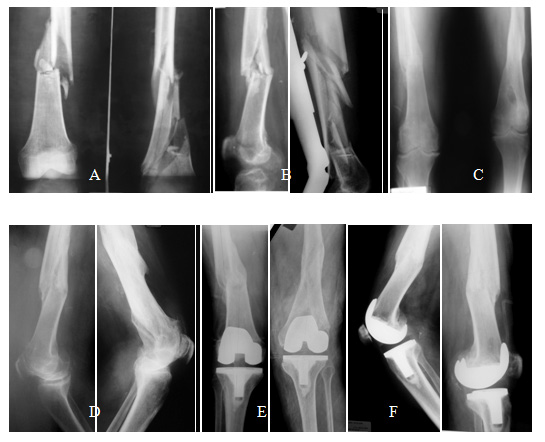

The causes of the deformity were: A- Post-traumatic in 8 patients (36.4 %): 3 due to malunion of femoral shaft fractures, 3 due to malunion of femoral supracondylar fractures and 2 nonunion of the proximal third of the tibia; B- Supracondylar Femoral osteotomy in 8 patients (36.4%): 7 varus (Figure 1) and 1 valgus; and C- Tibial osteotomy in 6 patients (27.2%): 3 Varus and 3 valgus osteotomies. We must point out that even if the majority of the valgus osteotomies of the proximal tibia create an extra-articular deformity, only those exceeding 10° have been included in this study.

Figure 1 A-70 year old man with valgus osteoarthritis of the right knee, a previous femoral varus osteotomy, an 11° femoral varus deformity and valgus anatomical axis of 13°. Note the limitation for using the femoral endomedular guide due to the deformity and the hardware. B- TKA with a valgus final axis of 3°. In this case we used an extra-medulary femoral guide. The femoral prosthesis stays centered in the epiphysis and appears as “not centered” with the femoral shaft.

There were 13 varus knees (average of intra-articular deformity of 9.2°) and 9 valgus knees (average of intra-articular deformity 16.6°). The extra-articular deformity was situated in the middle third of the femur in 3 patients (13.6%) (Figures 2 & 3), in the distal third of the femur in 11 (50%) (Figure 1), in the proximal third of the tibia in 6 (27.2%) and in the middle third of the tibia in 2 (9.1%). Regarding the type of deformity, all of the patients had a coronal deformity, 10 in varus (average 16.3°), 11 in valgus (average 14.4°) and 1 case with a medial displacement of the distal femoral segment of 3 cm. (Figure 3). In 6 patients, the deformity was biplanar, also with alterations in the sagital plane, 3 in flexion and 3 in extension, with an average of 19.7° and 8° respectively. No patients showed a significant rotational deformity.

Figure 2 Use of conventional X-rays as a puzzle to measure the limb`s axisA- 47 year old male showing a 2 site left femoral shaft deformity, consequence of a fracture. Valgus knee osteoarthritis, ROM 10° to 40°, femoral varus deformity of 18° and valgus anatomical axis of 23°. B- An All Poly TKA was made, obtaining a final valgus axis of 7°. In order to facilitate the access to the joint, an osteotomy of the tibial tuberosity was performed.

Figure 3 A and B79 year old man who suffered in 1974 a bilateral femoral shaft fracture that were treated non operatively. C and D- Malunion: Right femur with a medial displacement of 3 cm. of the distal bone segment and 13° of recurvatum, and left femur with a valgus deformity of 12° and 9° of recurvatum. Note the bilateral obliteration of the femoral canals precluding the use of long intramedullary guides. E and F- Bilateral non-simultaneous TKA, the left one 13 months after the right one.

Figure 4 -For the distal femoral cut planning, a line at 90° to the mechanical axis of the femur is used: A- If the line passes below both epicondyles, the intra-articular bone cuts should be enough to correct the deformity. B- If the epicondyle ligament insertions are compromised, a correcting femoral osteotomy at the apex of the deformity may have to be performed. C-For tibial planning, the projection of the tibial segment axis distal to the deformity is used. If the axis passes inside the tibial plateaus, the correction can be made through intra-articular bone cuts without compromising the knee stability. D- If it passes outside of the tibial plateaus, a correcting osteotomy may have to be accomplished.

Figure 5 A, B & C- 35 year old man, with terminal fibular Hemimelia of the left lower limb, homolateral knee osteoarthritis, previous femoral nailing and a 20° varus and 28° sagital antecurvatum tibial deformity, as a sequel of a lengthening treatment. D & E- AP severe knee osteoarthritis, posterior tibial  subluxation and Patella baja. F & G- AP and lateral view of the TKA. An osteotomy of the tibial tuberosity was performed.